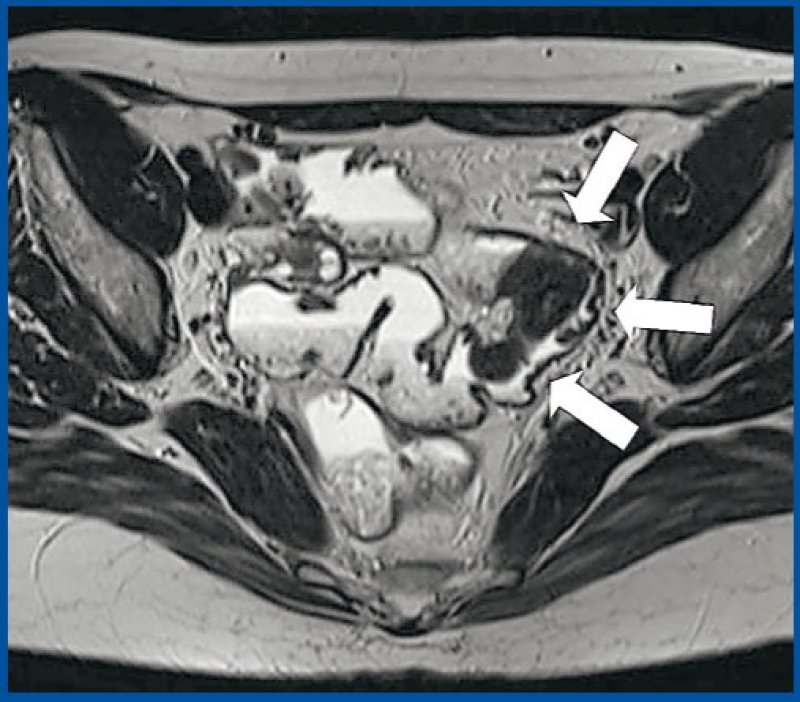

Who is at risk for colorectal cancer and is there anything you can do to prevent it? Divertikelkrankheit Divertikulose Divertikulitis Antireflux Info